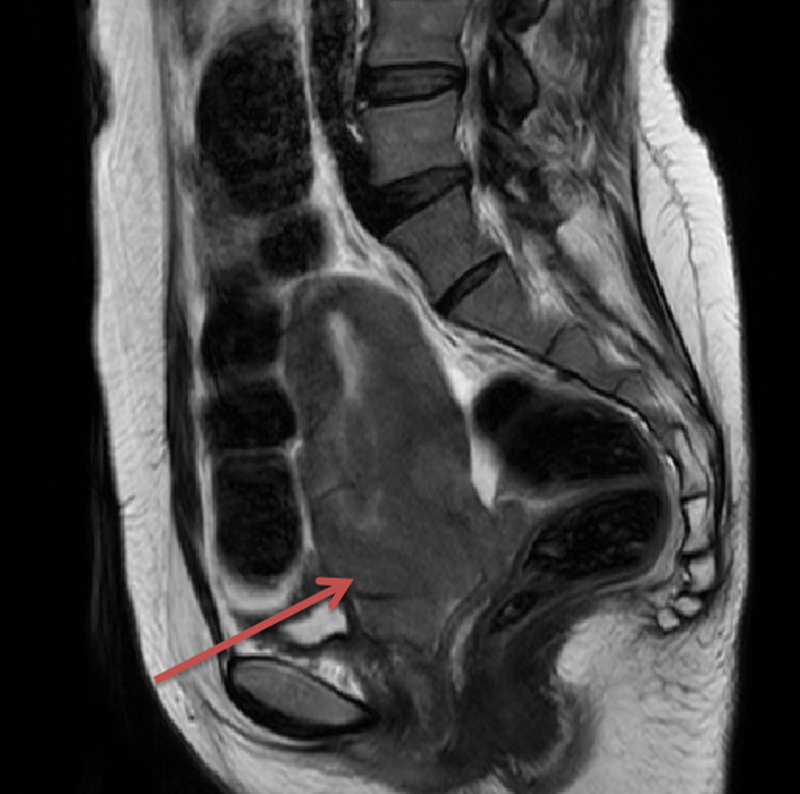

MRI检查:宫颈明显增大,呈软组织肿块影,T1W1呈低信号,T2W1-FS呈稍高信号,DW1序列呈高信号,ADC图呈低信号,增强后不均匀强化,601/IM6示较大截面范围约7.43*5.42cm,符合宫颈癌征象,病灶向上累及宫体下段,向下累及阴道上中段及穹隆,膀胱后壁、直肠前壁、两侧宫旁拟受侵犯可能,两侧盆壁、髂血管旁多发肿大淋巴结;右侧耻骨转移。盆腔内少量积液,右侧附件暂拟生理性改变。

10

图4. MRI结果提示宫颈明显增大,符合宫颈癌征象